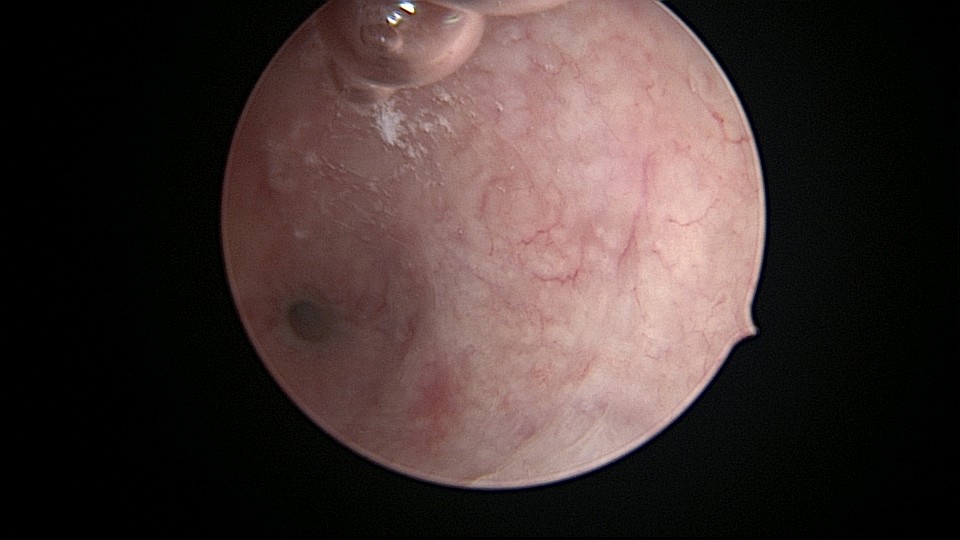

患者32岁,G2P0,自然流产2次,外院行清宫术,术后月经量减少一半。2019年6月市妇幼分粘,术后月经无改善,宫腔粘连复发,2020年11月宫腔镜探查,宫腔中上段幕状粘连,形成两个假的输卵管开口,双极电针分粘,恢复宫腔形态,显露正常的输卵管开口。2020年12月宫腔镜二探取球囊,宫腔形态正常,双侧输卵管开口可见,内膜充血。2022年5月自然妊娠,2023年1月剖宫产分娩一女婴(37+2)。现37岁,G3P1。